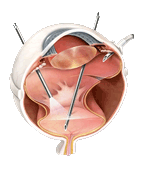

水晶体核落下に対する硝子体手術(左)や眼内レンズ落下に対する硝子体手術(右)や眼内レンズ混濁や度数違いでの眼内レンズ交換術

網膜剥離と白内障同時硝子体手術(左)や白内障のチン氏帯脆弱症例に対する眼内レンズ強膜内固定術(右)

硝子体出血や眼内炎や黄斑前膜など白内障同時硝子体手術(左)や白内障のチン氏帯脆弱症例に対する眼内レンズ縫着術(右)などを行っております。